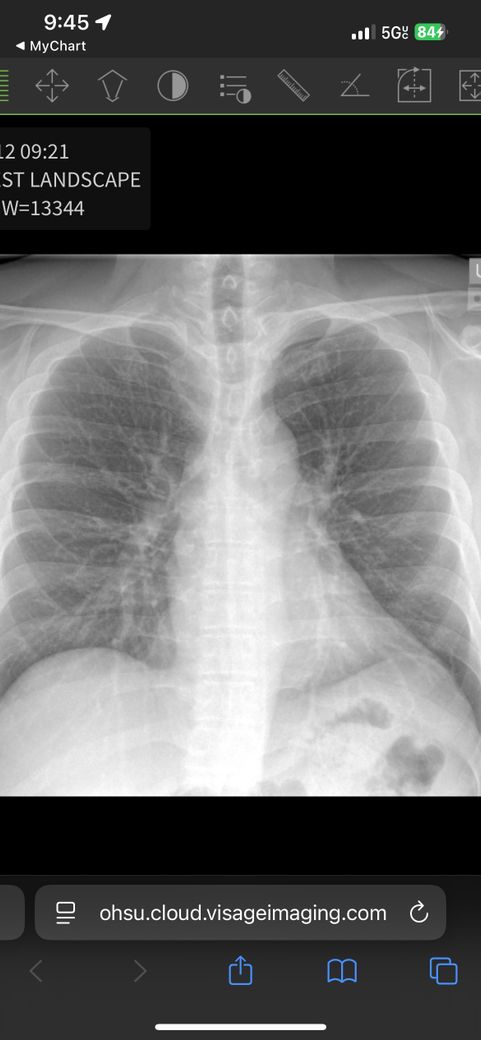

미국에서 흉부 통증으로 urgent care 방문후 엑 스레이 촬영했는데 사진 확인부탁드립니다

• 2번 째 사진

X-ray에 표시해주신건 1번 갈비뼈와 기관지입니다. 문제 없는 모습이니 걱정 안하셔도 되겠습니다.

흉부 통증의 경우는 호흡기 보다는 심장에 대한 진찰 및 검사가 필요하겠습니다.